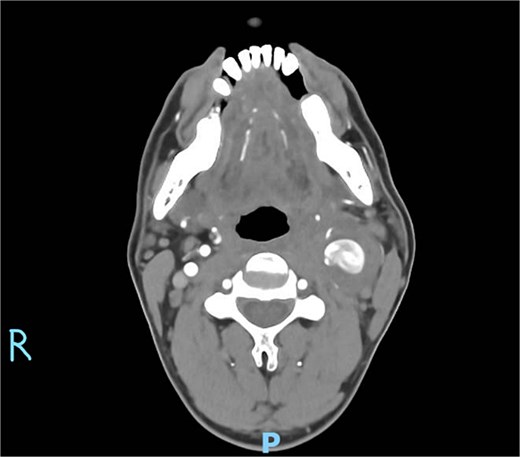

On physical examination, vital signs were stable. A tender, pulsatile mass was palpable in the left anterior triangle of the neck (Fig. 1). Ultrasound revealed a 21 × 16 mm aneurysm of the left common carotid artery (CCA) with prominent reactive cervical lymphadenopathy. This was further evaluated with CT angiography, which confirmed a left CCA aneurysm involving the carotid bulb (Fig. 2).

Axial CT angiography demonstrating the left common carotid artery aneurysm.